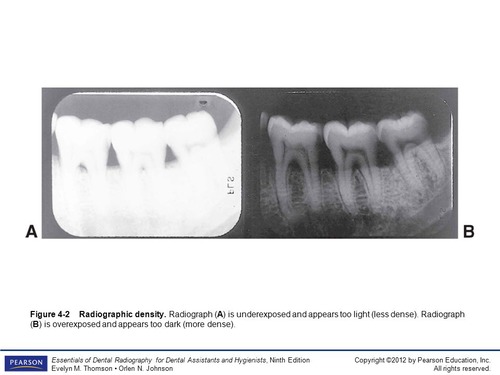

What is the density of a dental radiograph?

The darkness

If we increase kV, what happens to the density?

The image will appear darker

New cards

If we decrease kV, what happens to the density?

The image will appear lighter